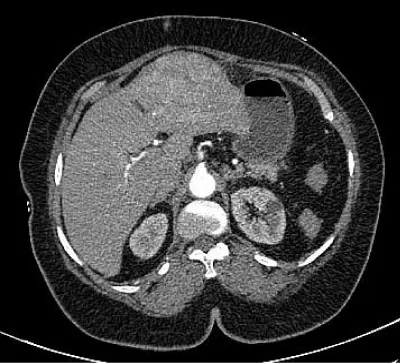

62 years diabetic, hypertensive and obese (body mass Index 38) patient with hepatitis C positive status suffered from pain right side abdomen. She got detected with a liver mass on ultrasonography. There was no history of upper gastrointestinal bleed, abdominal distention or disorientation. She was evaluated further with triphasic CECT liver; which revealed 7X10X8 cm mass in the left liver involving segments II, III & IV. This mass showed an early enhancement in the arterial phase and delayed washout suggesting hepatocellular carcinoma (Figure 1). Underlying liver parenchyma also showed some signs of cirrhosis. PET scan confirmed no distant metastasis. Biochemical analysis reported hemoglobin 13.5 g%, total leukocyte count 7700/ cmm, platelets count 2.56 lac/cmm, serum bilirubin 0.8 mg, prothrombin time 12.3sec and INR 1.08. This patient was classified in Child Pugh class A (score 5). She was evaluated for signs of portal hypertension. Upper gastrointestinal endoscopy was normal and portal vein pressure was 11 mmHg suggesting mild portal hypertension. Future liver remnant by automated liver volumetric analysis for left hepatectomy excluding middle hepatic vein was 76% and for left hepatectomy including middle hepatic vein was 70%.